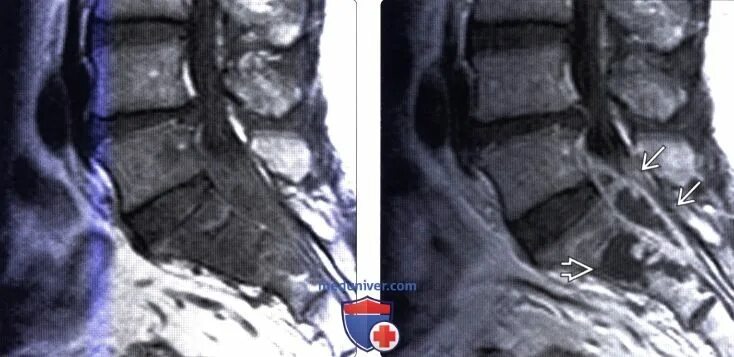

Деформация дурального мешка поясничного